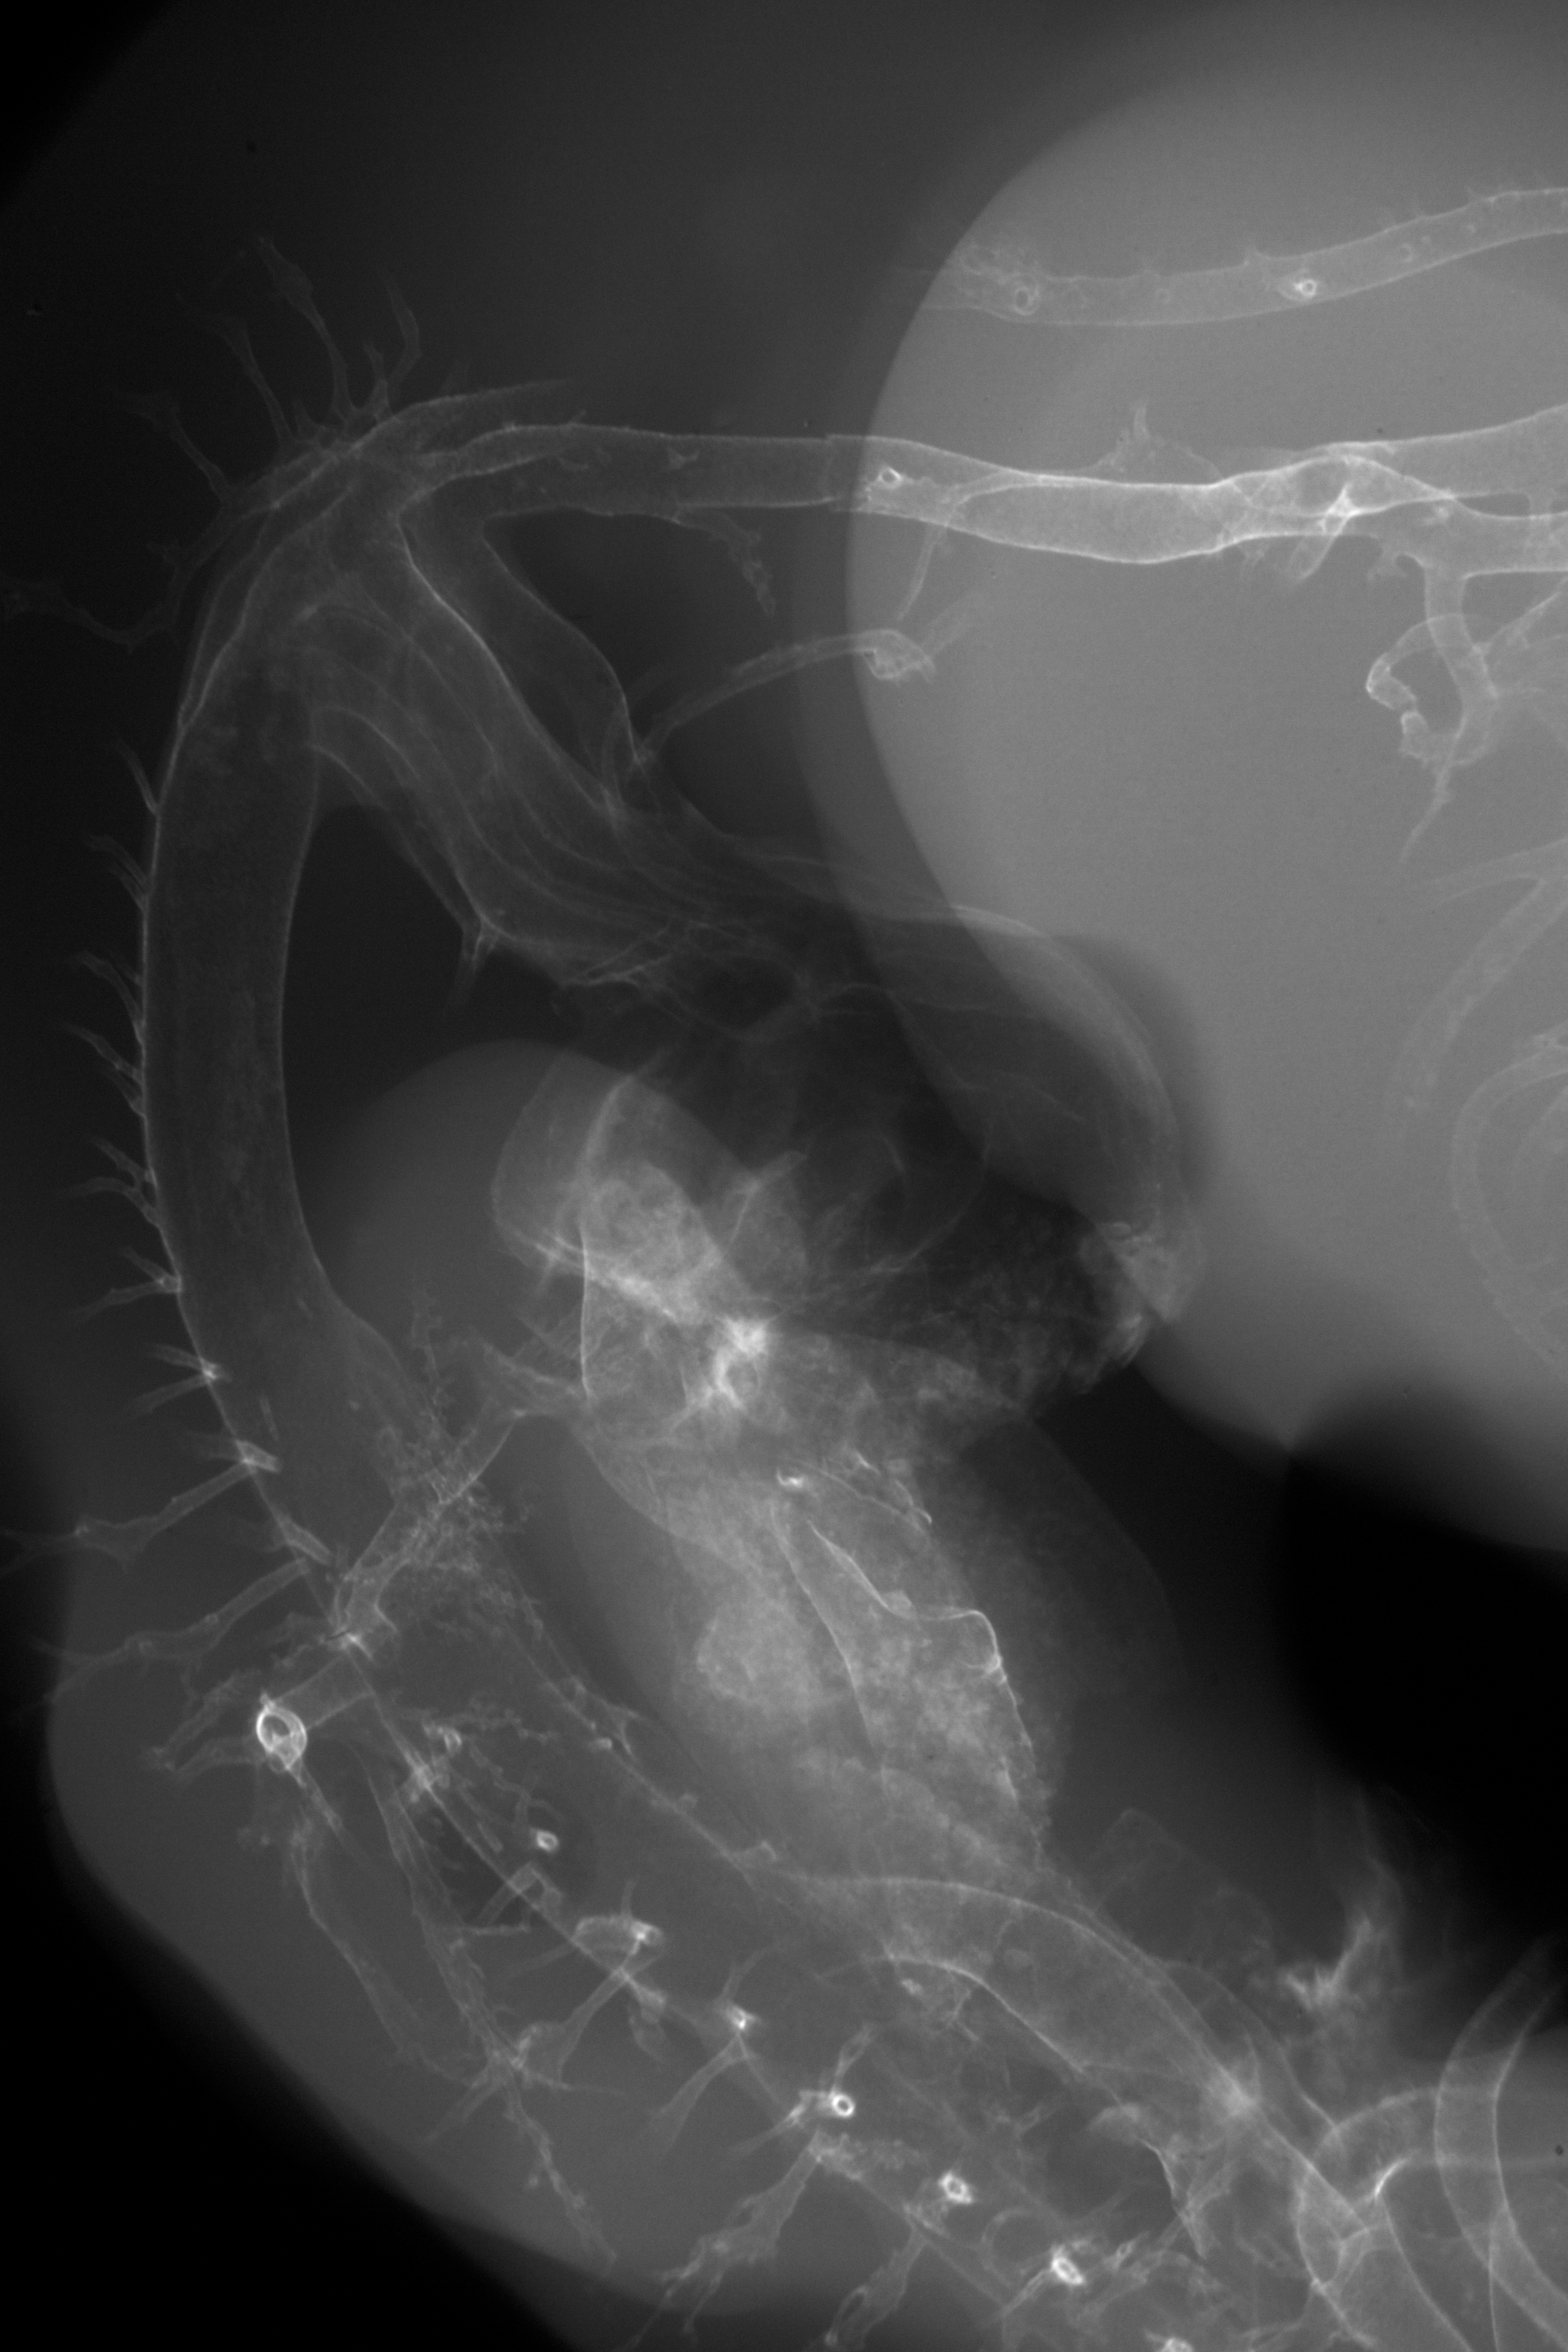

Chick Embryo Microangiography

Hamburger-Hamilton (HH) Stage 27 (approx. 5 - 5.5 days)

Stereo X-Ray Micrographs